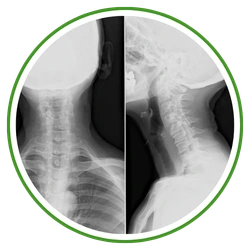

Chiropractors take x-rays to see the internal condition of the spine. X-rays also reveal if there are any underlying spinal disorders, such as arthritis of the spine, abnormal development, disc disorders, bone spurs, and spinal deterioration.

Having an x-ray taken before any adjustment helps chiropractors make a correct diagnosis. Combining x-rays with other exams will benefit the patient ultimately.